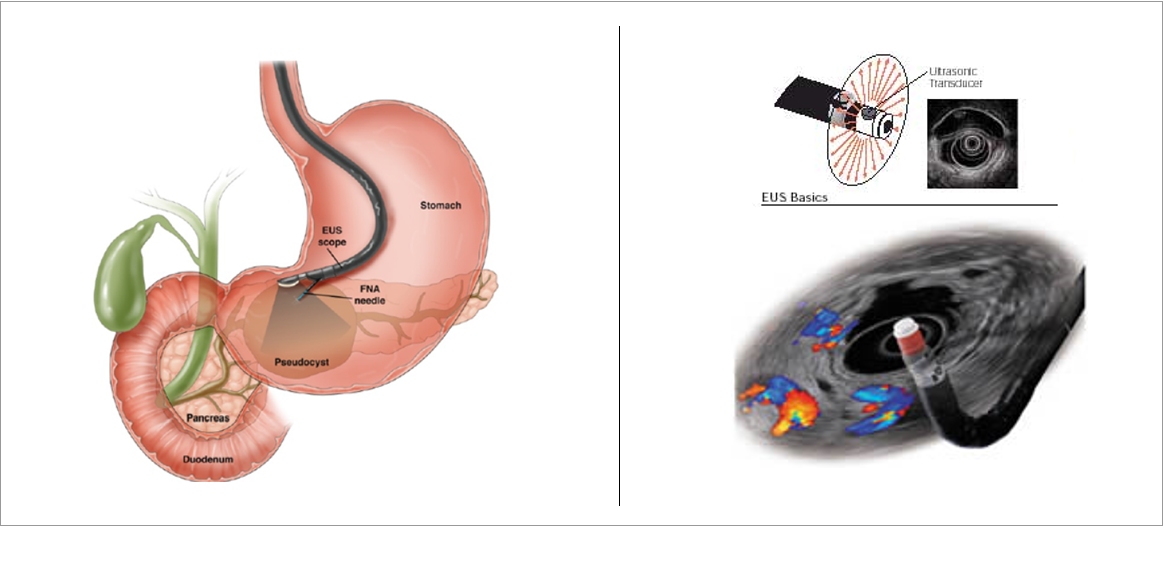

Endoskopik ultrason (EUS), aşağıdakileri harmanlayan özel bir işlemdir:

Endoskopi— Sindirim sistemin iç yüzeyine bakmak için ucunda kamera olan esnek cihazın kullanılmasıdır.

Ultrason — Bağırsak duvarının ve yakındaki organların veya yapıların ayrıntılı görüntülerini görmek için yüksek frekanslı ses dalgalarının kullanımıdır.

Endoskopik Ultrasonografi (EUS) hem sindirim sisteminin iç yüzeyini görür, hem de duvarın katmanlarını ve duvarın arkasındaki organları görür. Bir anlamda EUS duvarın arkasını görebilmektir.

EUS cihazı, kameralı ve ucunda ışık olan ince, esnek bir tüptür. Cihazın uç kısmına küçük bir ultrason probu eklenmiştir.

İnce iğne aspirasyonu (FNA): Bir doku örneği almak gerekiyorsa, doktorunuz biyopsi almak için ince bir iğneyi endoskoptan geçirir ve ultrason görüntüsünü altında görerek biopsi alır. Bu işlem yapılırken hasta uyuduğu için ağrı sızı olmaz.